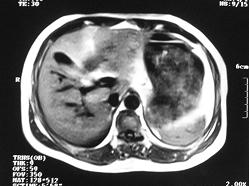

男 45岁。体检b超发现肝脏一低密度病变,怀疑是血管瘤,来ct检查。

ct平扫:在肝右后下叶一直径约2厘米的圆形低密度病变,ct值约32hu。

增强三期都未强化。后经mri检查,t1wi及t2wi为等信号,与肝脏等信号。